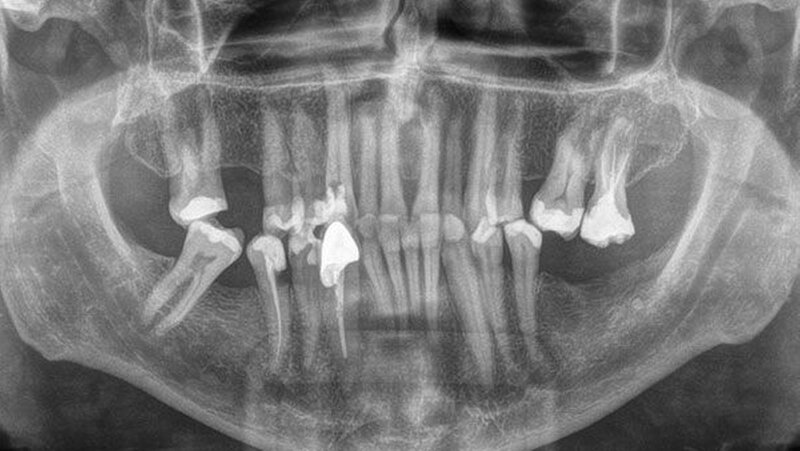

Bereits auf der Panoramaschichtaufnahme konnte man die beachtliche Größe des Extraktionskandidaten erkennen. Nachdem Lukas nach dem Eingriff den Zahn vermessen und mit den auf der Internetseitewww.guinnessworldrecords.deaufgeführten Daten des aktuell längsten extrahierten menschlichen Zahns verglichen hatte, war klar: Neuer Weltrekord - mit 37,2 Millimetern war dieses Exemplar einen halben Millimeter länger alsder aktuelle Weltrekordhalter aus Indien!